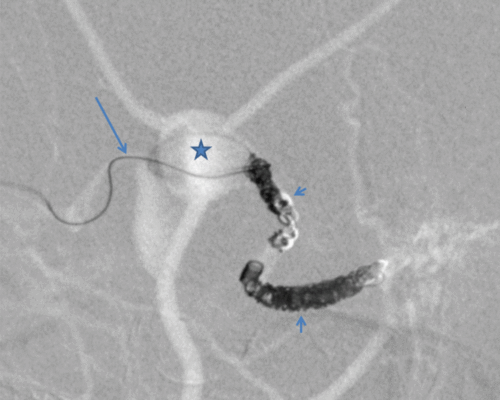

Figure 1 – Position of the microcatheter (long arrow) in the draining vein. A large venous aneurysm (star) has been passed successfully with the catheter. Multiple coils (short arrows) have already been placed to occlude the fistula.

We treated a complex dAVF with multiple feeders from the middle meningeal artery and dural branches of the ophthalmic artery in a 76-year-old male patient by means of a new retrograde, transvenous endovascular approach that achieved the complete occlusion of the fistula in a single procedure. The draining vein of the dAVF (grade Cognard IV) showed two large aneurysmatic pouches in the middle cranial fossa with high risk of severe bleeding. The patient gave informed consent for the procedure and for the use of his data.

As a transarterial approach was considered not effective due to the configuration of the fistula, transvenous embolisation via the internal jugular vein using a flow-directed microcatheter with microwire guidance (MarathonTM catheter, MirageTM microwire, Medtronic, Minneapolis/US) was preferred. The rationale of this approach was to exploit the catheter’s flexible design to not cause artificial rupture of the venous aneurysms while passing them to reach the fistula.

However, so far none of the commercially available coil systems was suitable for usage via a flow-directed microcatheter. On the other hand, we were concerned to cause a rupture of the venous aneurysms or to be unable to reach the fistula point through any catheter stiffer than a very flexible flow-directed microcatheter. The solution to this problem came through a new monopolar detechable coil system (ED CoilTM, Kaneka, Tokyo/Japan) which is explicitly usable via flow-directed microcatheter. By using this system, we successfully occluded the fistula with a total of 20 detachable microcoils and avoided the intravenous application of glue which could have been unpredictable and harmfully distributed against the high arterial flow. Five days after the procedure, it would have been possible to discharge the patient without any further discomfort.